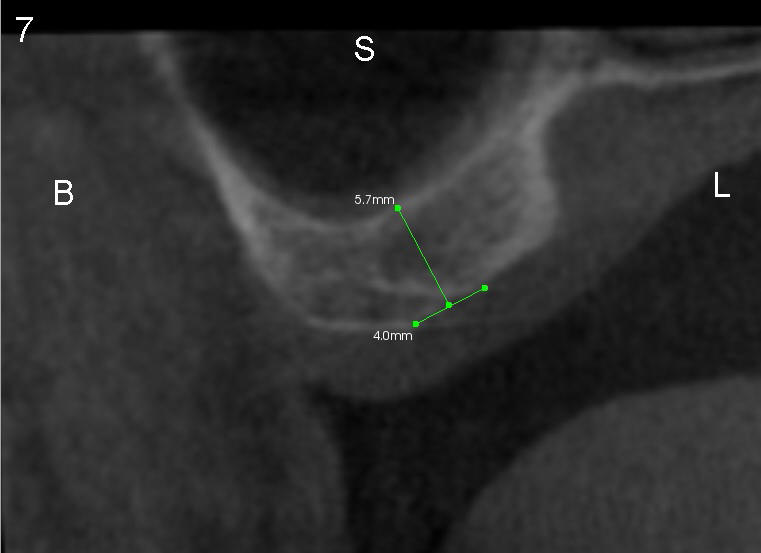

Fig.7,8 are CT coronal sections, showing #2 ridge morphology and implant design, respectively.